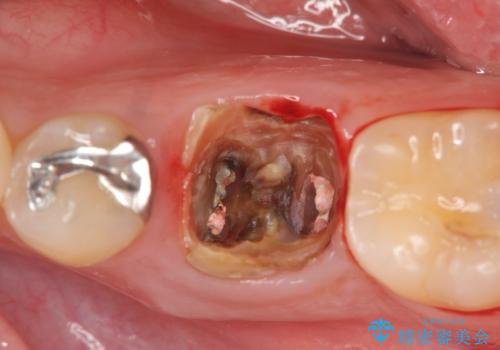

- 銀歯の奥歯で噛むと違和感・痛みがあるとのことで検査・治療を求めて来院されました。

銀歯を除去して見ると内部で虫歯が再発し、歯の辺縁は破折し保存が難しく抜歯をしなければいけない状態でした。

抜歯後ブリッジとインプラント治療を検討・相談し、より周囲の歯を削らずに済むインプラント治療を希望されたのでインプラントによる機能回復を計画します。